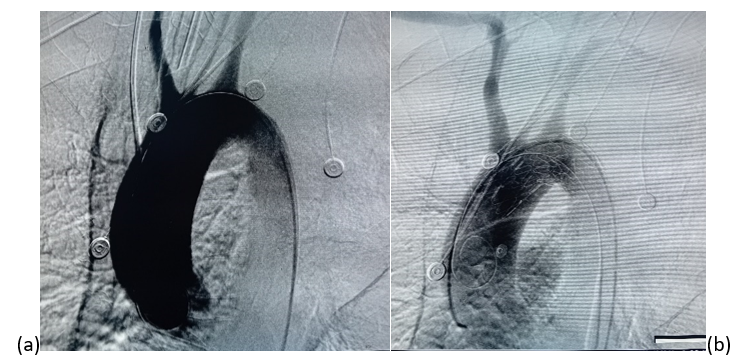

(a) Before stentgraft deployment, showing contrast extravasation indicating the presumed site of the malignant aortoesophageal fistula. (b) Completion angiogram after successful deployment 26 × 26 × 160mm stent graft with sealing of the aortobronchial fistula.